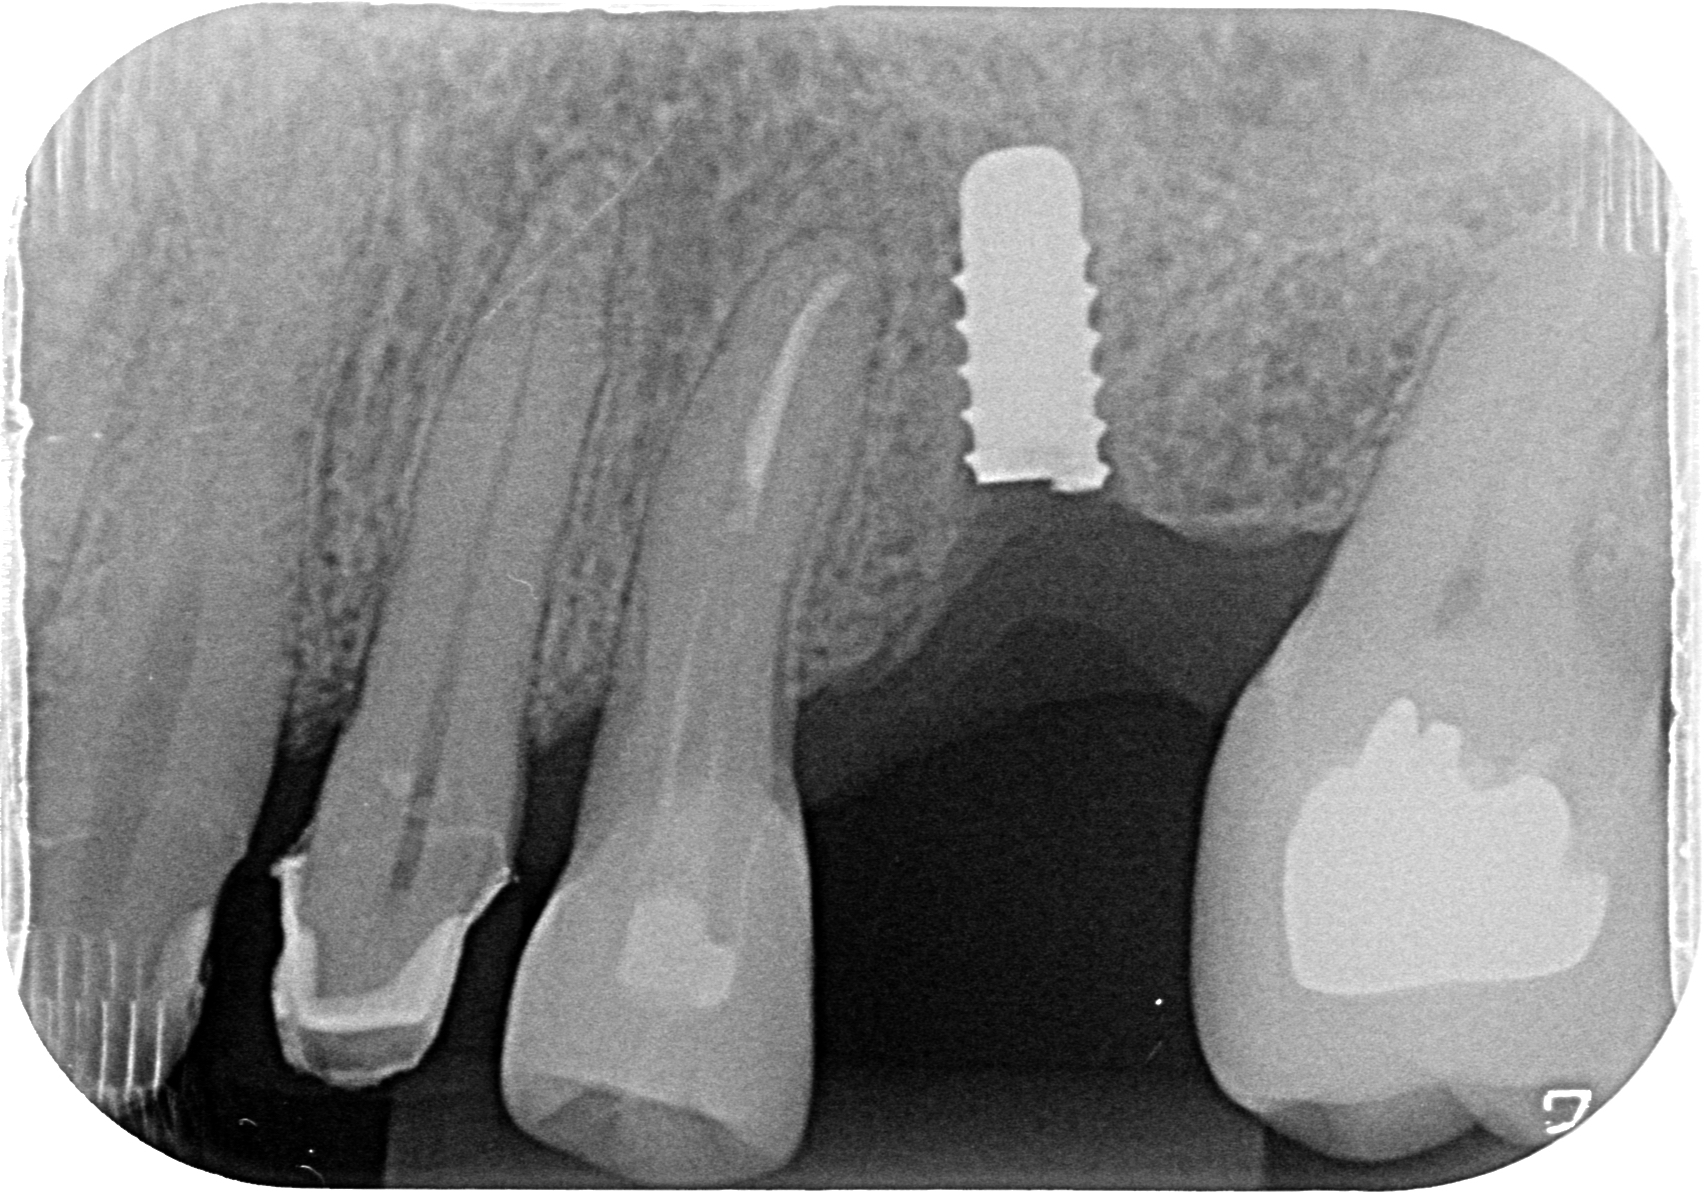

dental implant removal complication pain poor position crooked implant explantation kazemi oral Dental Implant Explantation Dental implants, which are mobile or show only little residual bone‐to‐implant contacts, can usually be removed with instruments, which. When removing an osseointegrated oral implant, factors such as the implant's design, proximity to important structures, and the. In the event a removal of a straumann implant is needed, this guide provides rules and instructions. Dental implants have become the leading. Dental Implant Explantation.